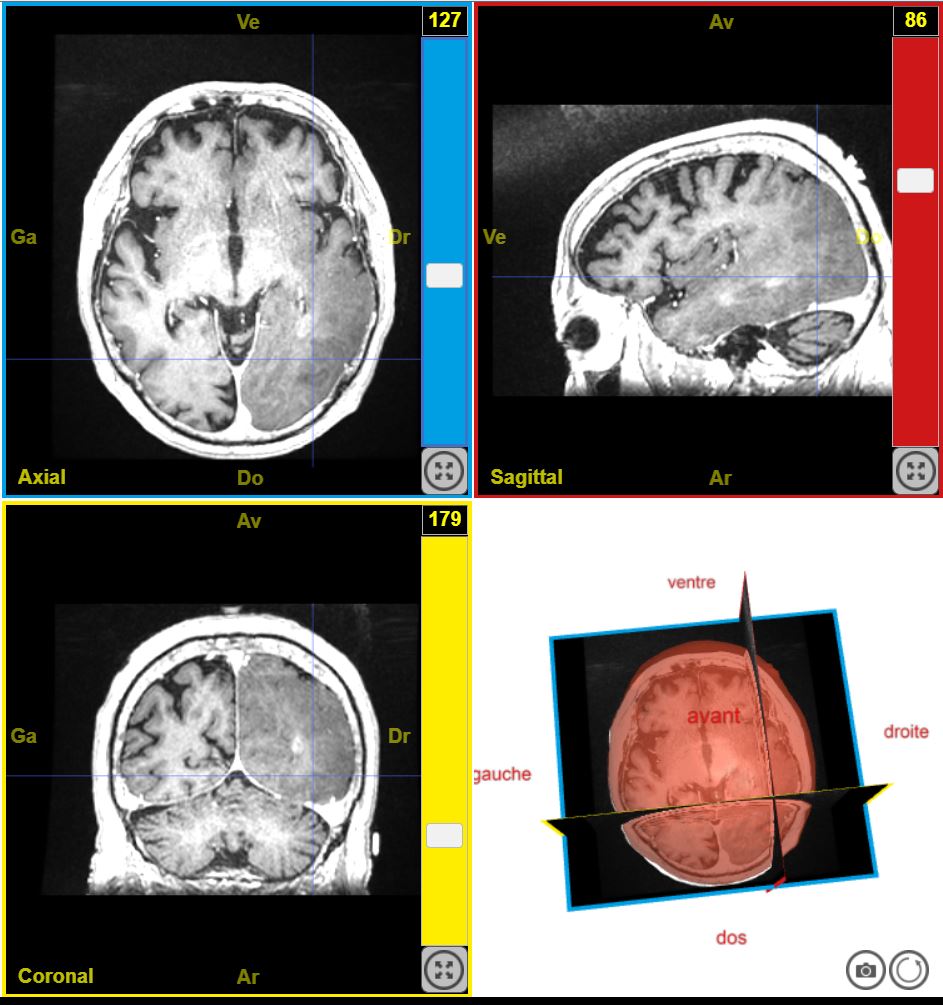

12224PathologieTumeurTroubleSensitifGauche T1.

Par Sandrine Beaudin